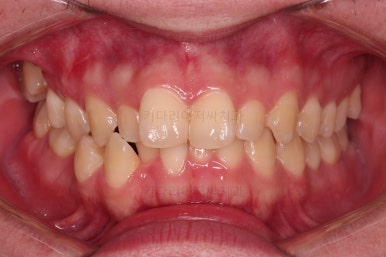

부산교정치과 초진 시 입안의 모습입니다.

앞니가 삐뚤어서 결손치아가 없었더라도 교정치료를 원하셨던 상황이었고요.

오른쪽 어금니 맞물림은 결손치아도 그렇지만 전반적인 앞뒤 차이가 있는 부정교합이 있었어요.

웃을 때 정렬되지 못한 치열 때문에 미적으로 좋지 못하네요.